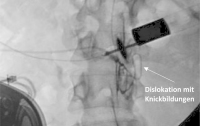

Abbildung 1: Komplikationen – Spinaler Katheter.

Abbildung 3: Durchleuchtung mit Darstellung des spinalen Katheters nach Kontrastmittelapplikation.